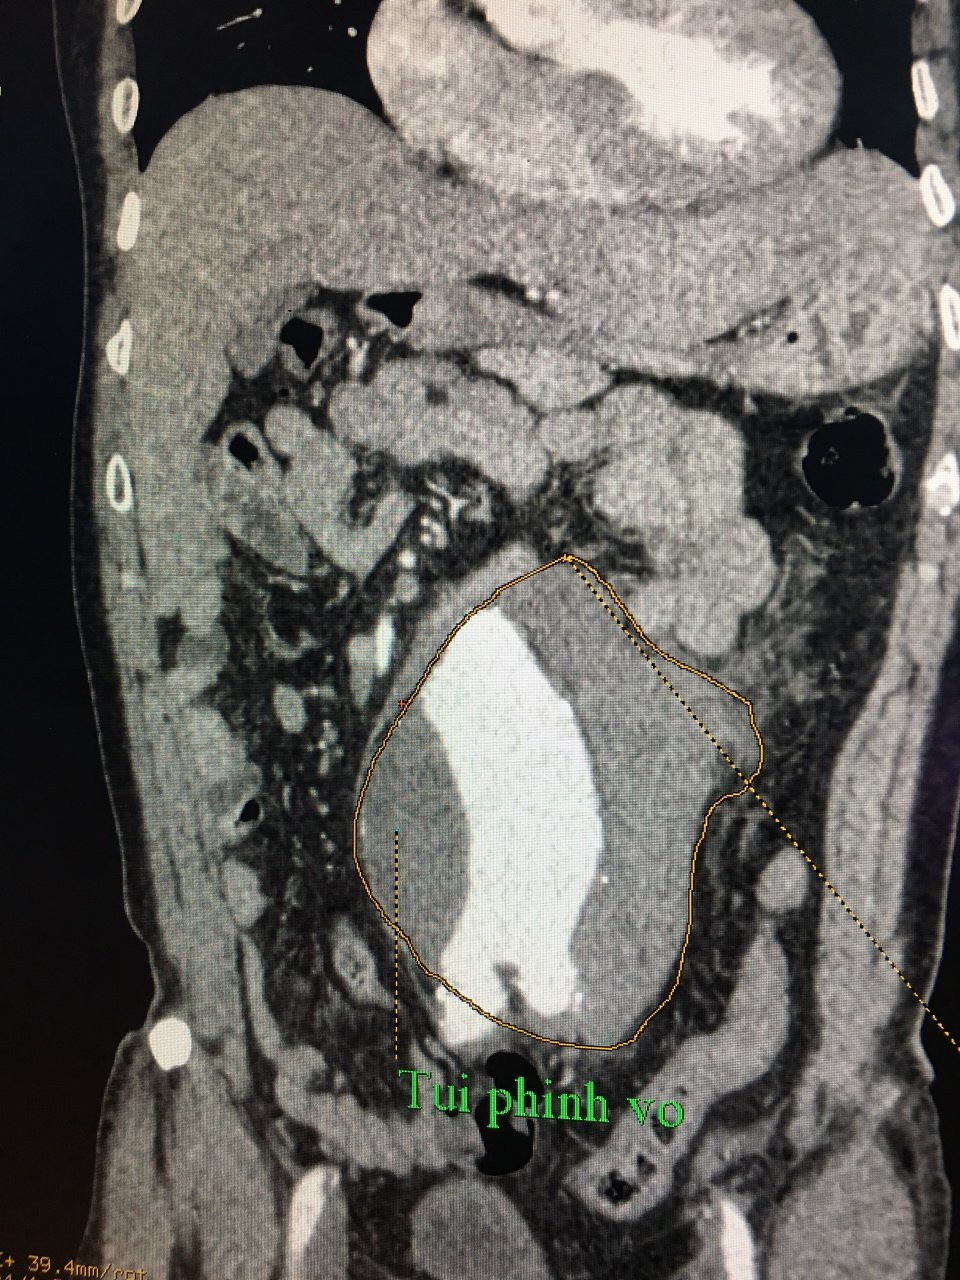

Qua thăm khám các bác sĩ xác định đây là tình trạng cấp cứu về ngoại khoa nên tiến hành  thực hiện khẩn siêu âm tổng quát, chụp cắt lớp vi tính mạch máu có cản quang. Kết quả CT-Scan cho thấy, ông Vinh bị vỡ phình động mạch chủ bụng đoạn sau chỗ chia động mạch thận đến chỗ chia động mạch chậu, đường kính 8.3 cm, chiều dài 10cm, có tụ máu sau phúc mạc.

Suýt chết vì phát hiện khối u quanh rốn đập theo nhịp tim nhưng không đi khám ảnh 1Vị trí túi phình vỡ.